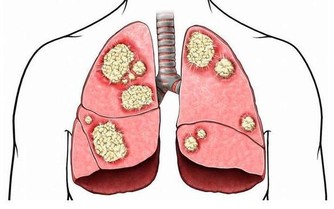

很多人都認為,只有年紀大的人,才會出現血管問題,實則不然,生活飲食熱量與脂肪的過多攝入,運動的減少,壓力增大,導致我們的血管年紀輕輕就開始老化,血管的彈性下降,血液流動速度受阻,最終因缺血而引起心、腦血管疾病。